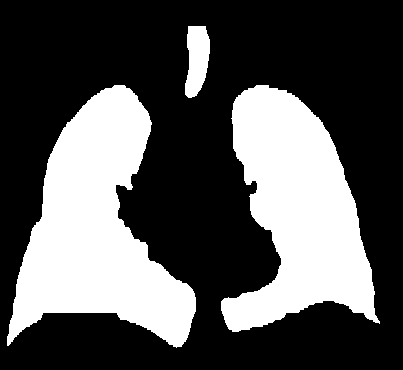

这个好理解,一般来说CT值的范围是-1000-+1000,而基于简单的观察,肺部就是胸腔内两个大的空洞,所以可以首先对图像进行二值化处理,这里是将CT大于-300的位置置为1,小于-300置为0,这样就将数据分为了三部分,外部空气,内部空气,躯干组织。如下图所示。

利用种子填充算法,将外部的空气和内部的躯干分割出来,给定两个种子,一般就能分出来。分割的效果如下。然后再用阈值图像减去这个躯干就能得到初步的肺部mask。此时肺部的值是1,组织值是0。